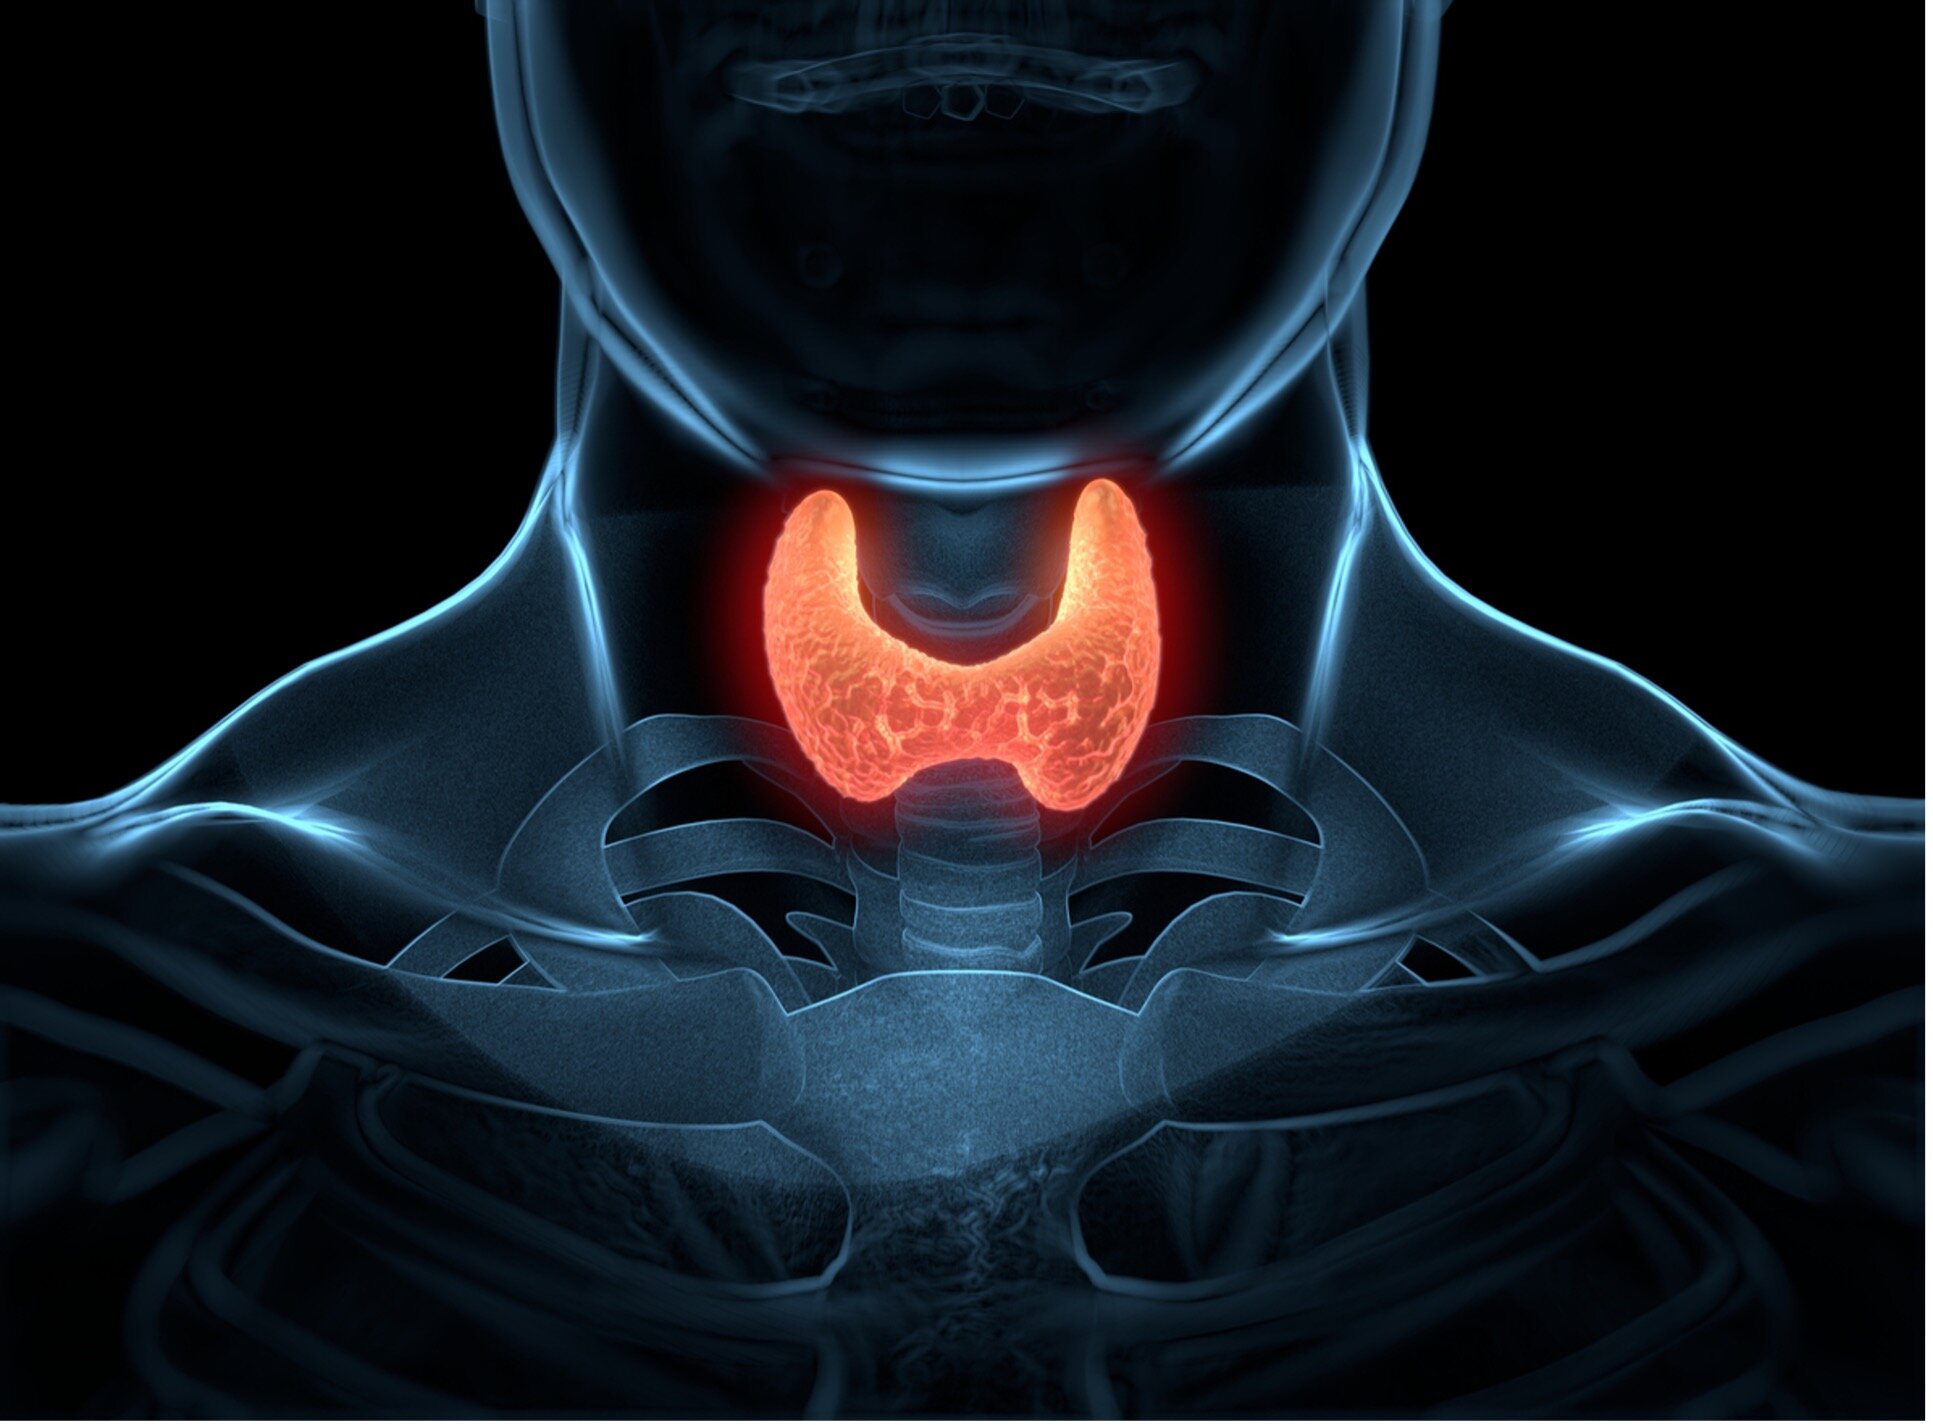

Эндокринология для начинающих: основы и важные аспекты